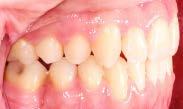

En las fotografías intraorales (Figura 3) observamos una clase II molar bilateral, clase II canina derecha, clase III canina izquierda, apiñamiento severo superior y moderado inferior, presencia de mordida abierta anterior y posterior a nivel de premolares (Figura 4), forma de arco triangular en la arcada superior y forma de arco oval en inferior, ausencia del OD 46 y presencia de un diente supernumerario.

Figura 2. Fotografías extraorales frente y perfil. Figura 3. Fotografías de frente, lateral derecha, lateral izquierda.

Figura 4. Vista oclusal superior e inferior. Figura 5. Frente, perfil.